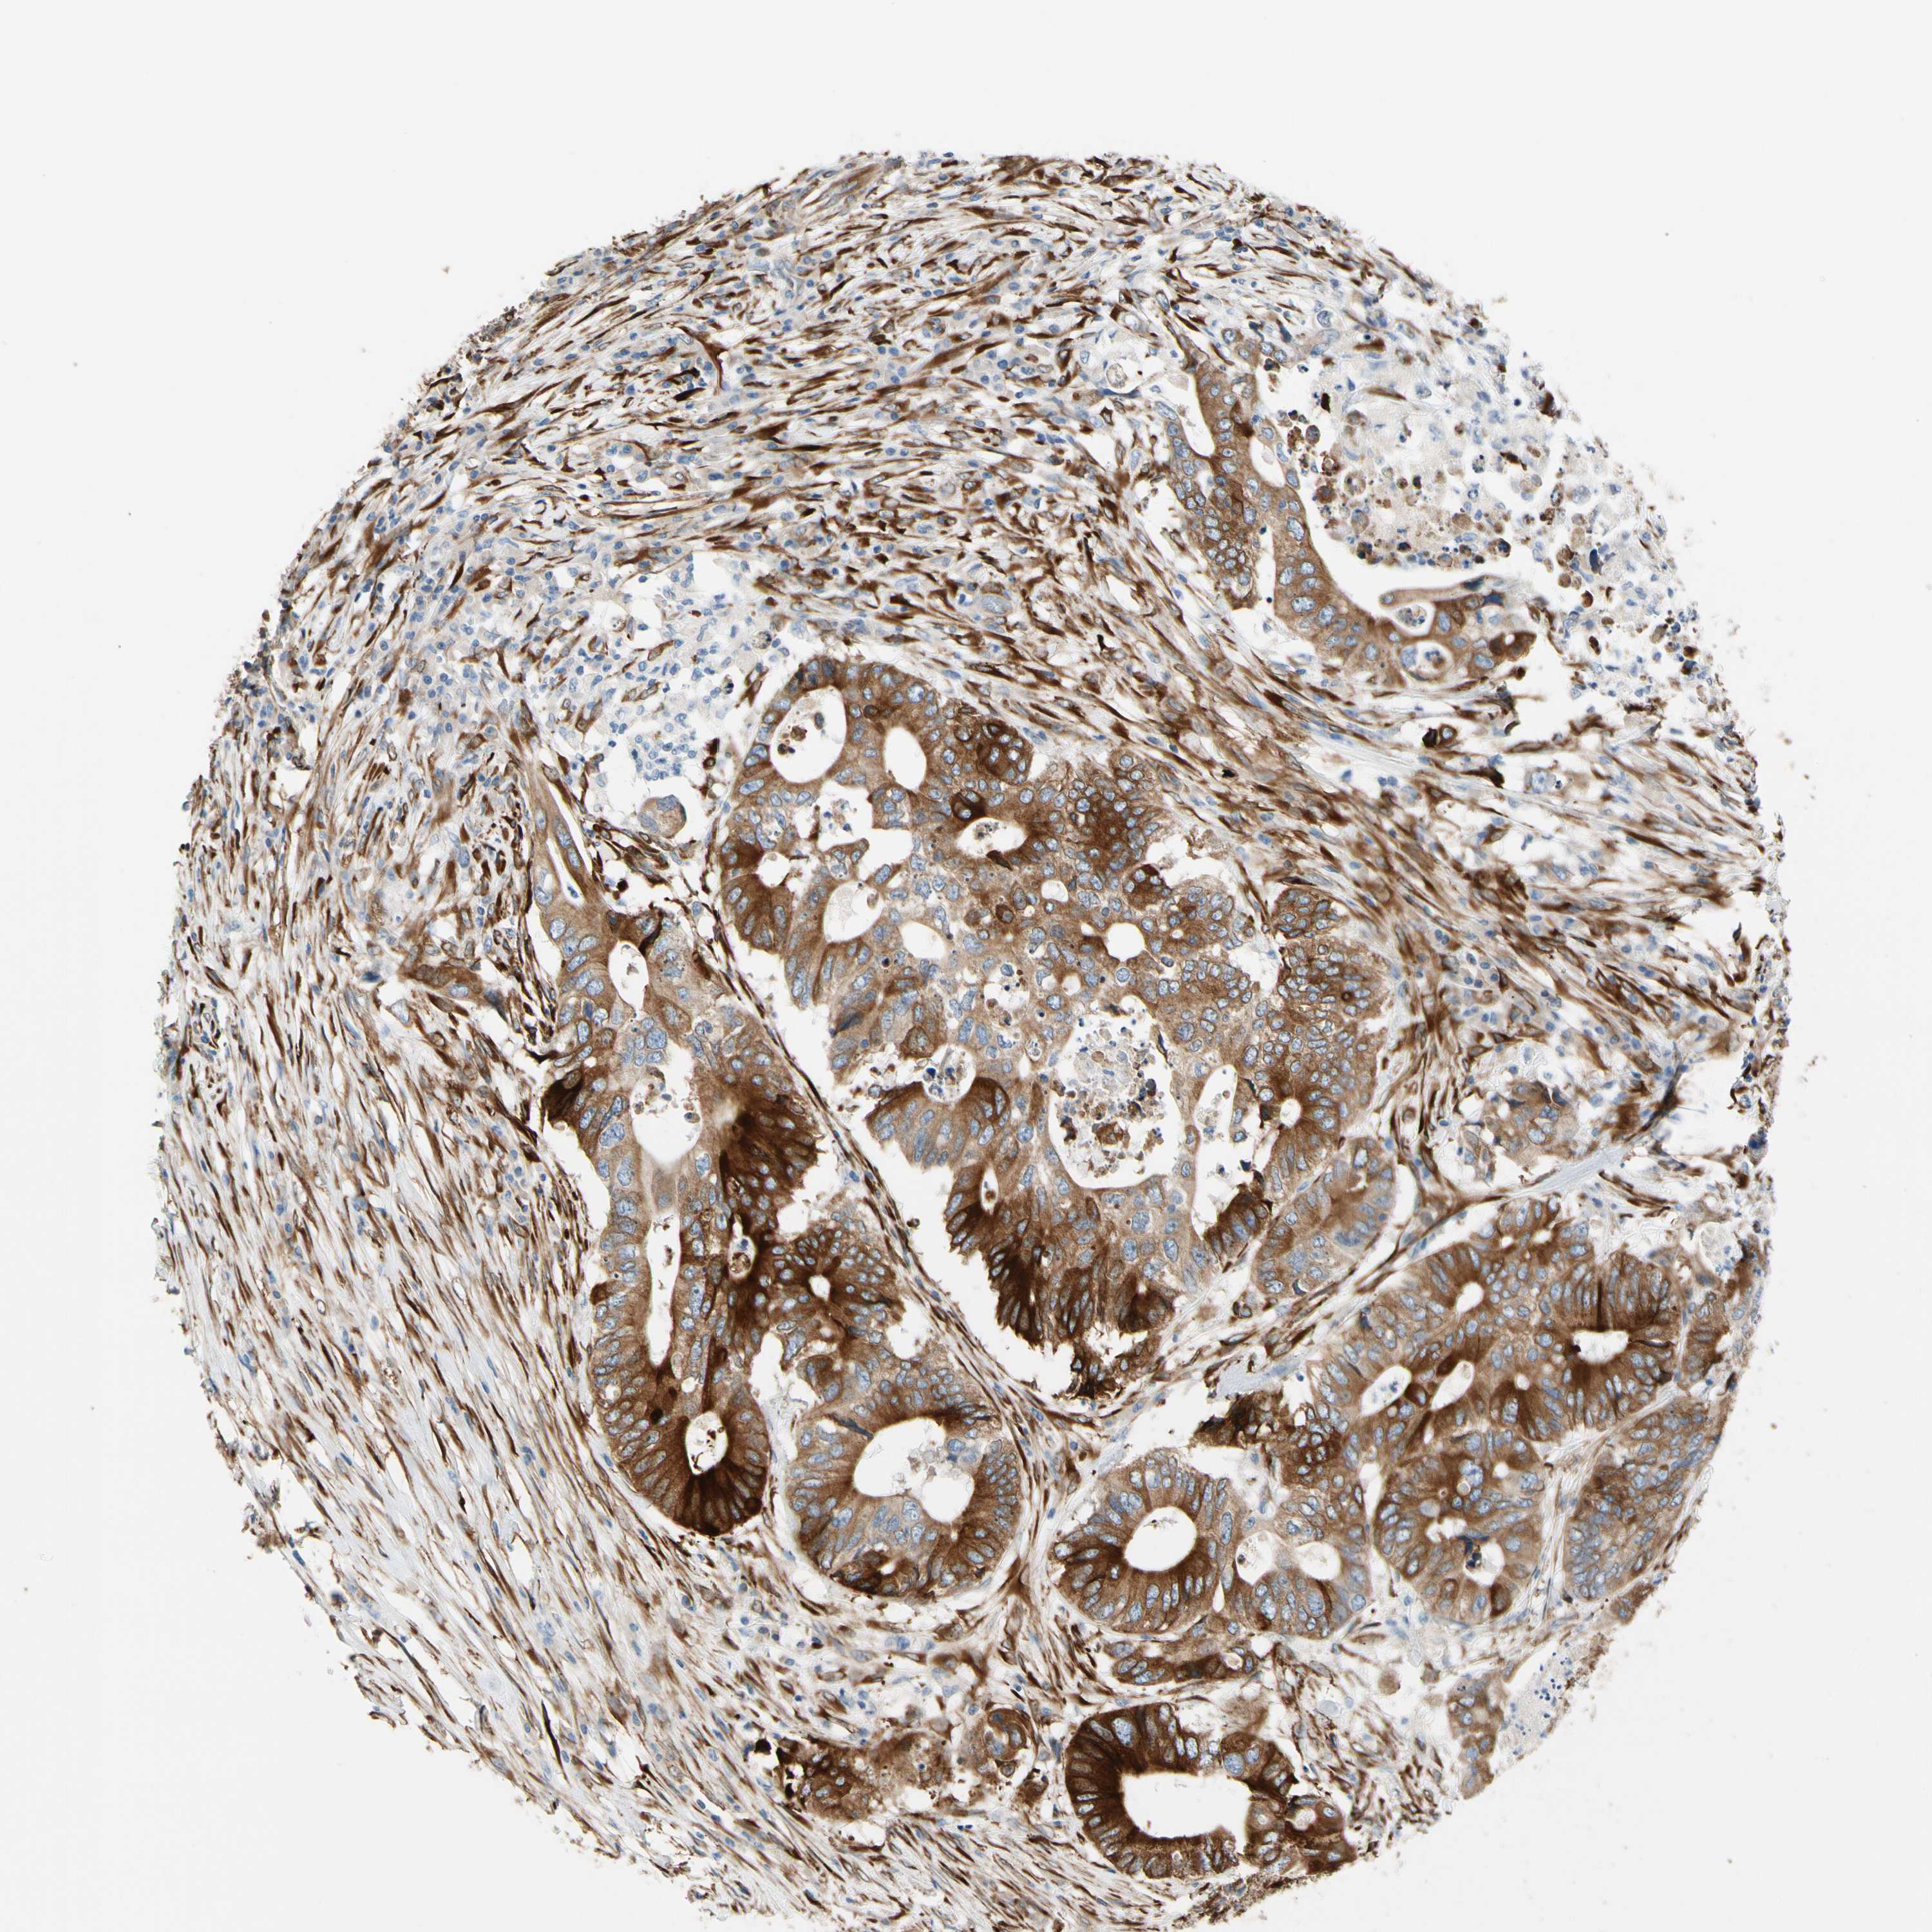

CANCER COLORECTAL CANCER Show tissue menu

Colorectal cancer

Human cancer

Colon adenocarcinoma